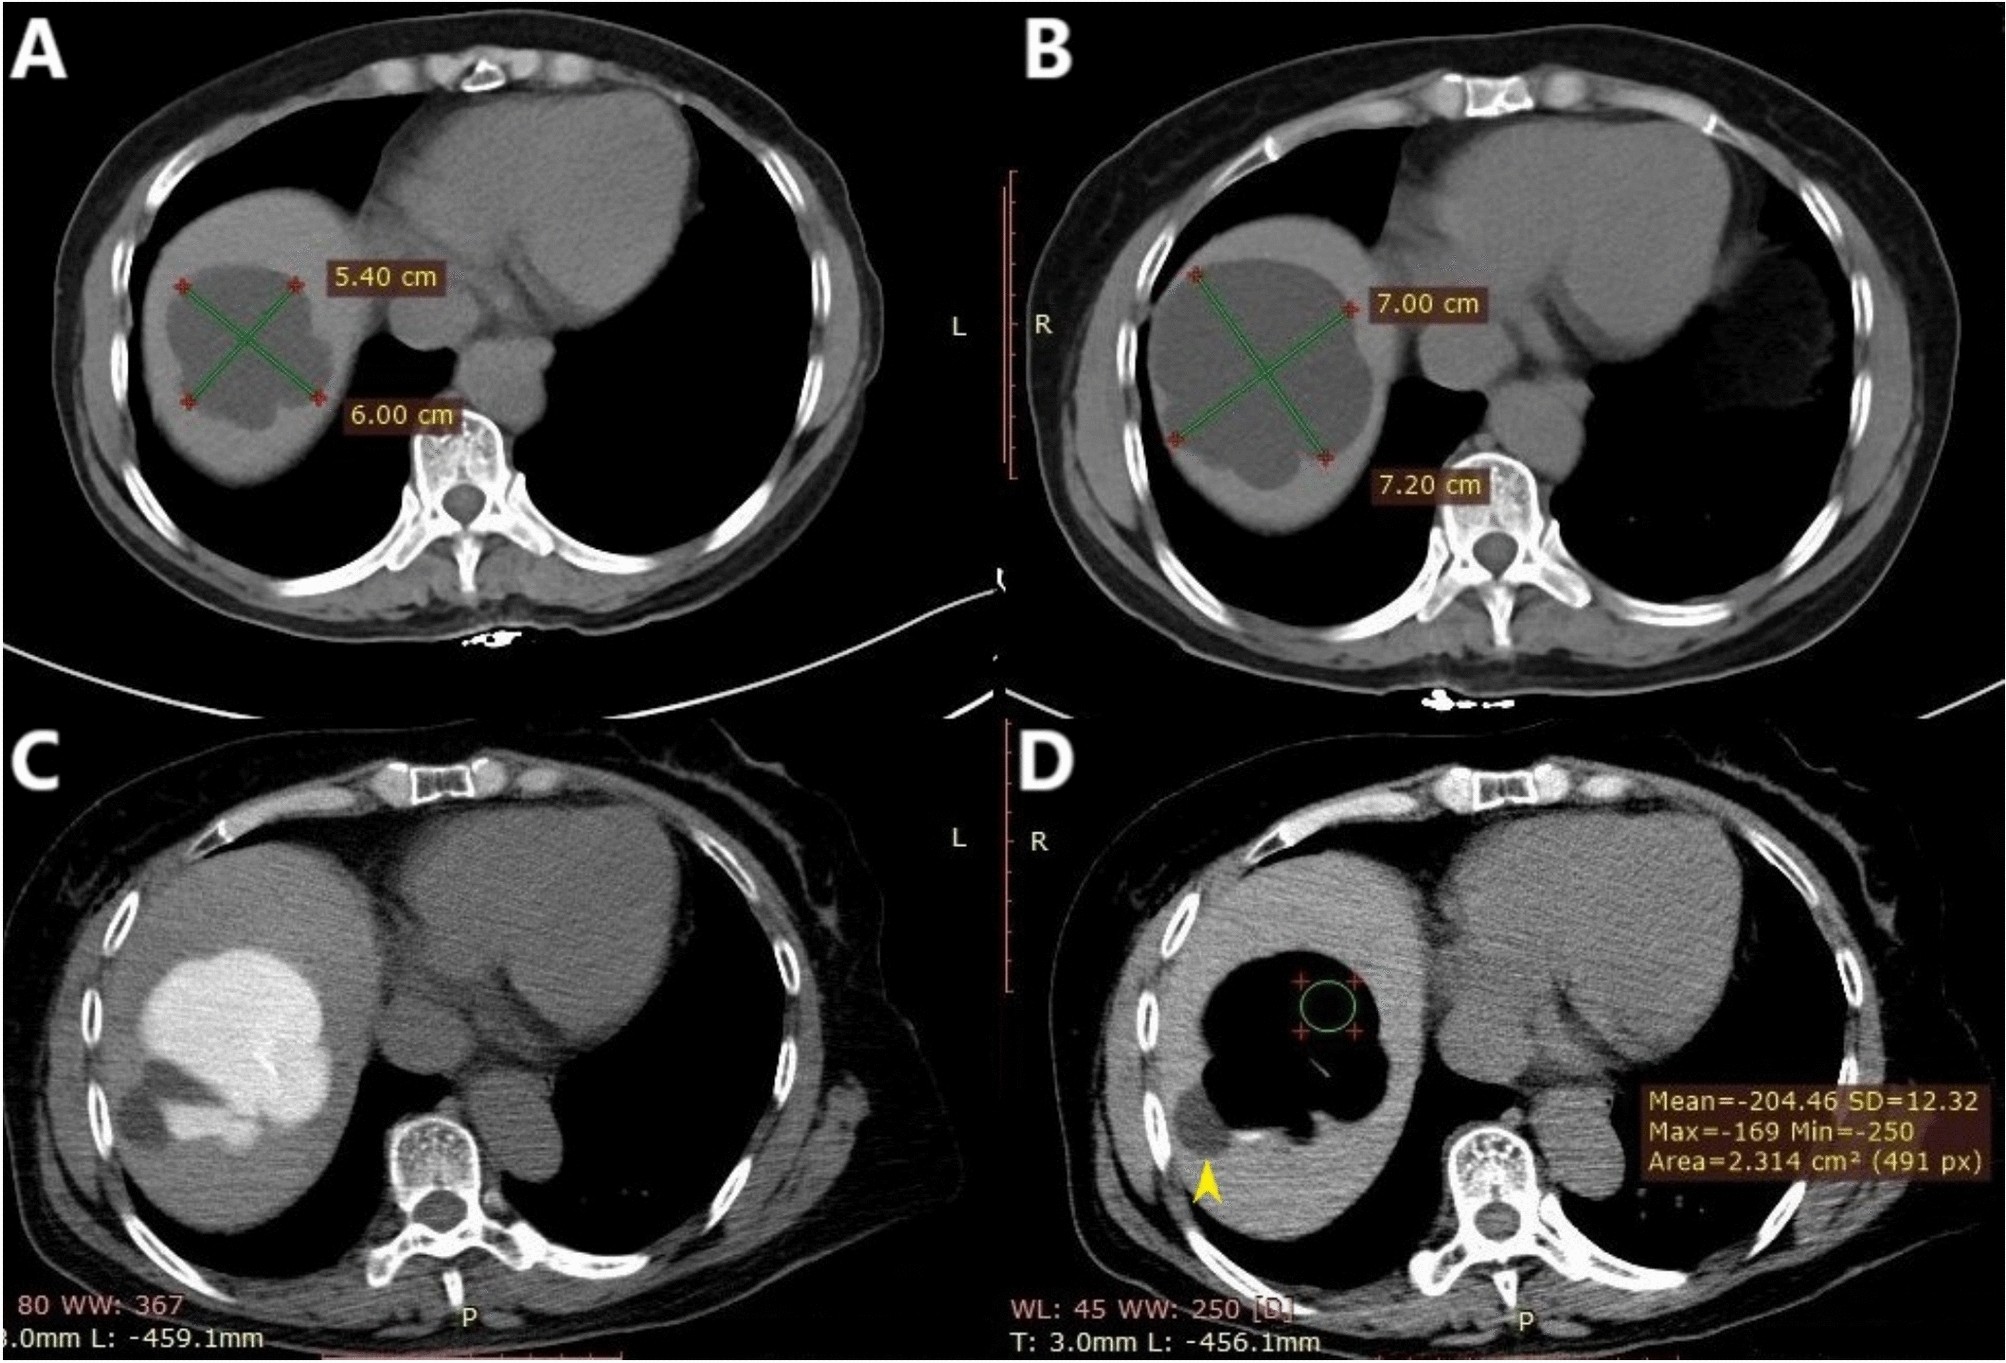

Fig. 1

A 57-year-old woman presented with an enlarging hepatic cyst. The simple hepatic cyst (approximately 3–4 cm in size) was accidentally discovered in 2016 via ultrasound. CT performed in May 2018 and November 2019 revealed progressive enlargement of the cyst. The procedure was performed at Center A using the modified technique, and the patient’s prior (A, B) and interprocedural (C, D) CT images are shown below. (A) In May 2018, the cyst size was 5.4 cm × 6.0 cm × 3.6 cm. (B) In November 2019, the cyst size was 7.0 cm × 7.2 cm × 4.6 cm. Its volume increased from approximately 60 mL in May 2018 to 121 mL in November 2019. (C) In December 2019, the patient underwent percutaneous drainage. The needle tip was inserted close to the deep cyst wall, after which the contrast agent was injected. (D) The CT value of the intracystic fluid was − 204 HU, suggesting that the ethanol concentration exceeded 90%. A small cyst (yellow arrowhead) adjoining the large cyst was not treated.